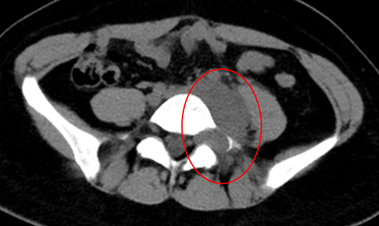

患者为54岁女性,自幼发现全身多发皮肤、皮下结节,并持续增多、变大,其中左臀部肿物尤为明显,因短时间内生长迅速、影响正常行走和排便功能来诊。患者体表可见大量散在皮肤结节、牛奶咖啡斑,MRI提示肿物信号混杂,膀胱、子宫、直肠明显受压右移,CT示该肿物跨盆腔内外,较大层面范围约13.5×8.7×13cm,密度欠均,夹杂囊变,累及左侧闭孔内肌、梨状肌、肛提肌及左侧外阴。

王伟东副主任团队根据患者临床症状、影像学特征及既往病史分析,确认患者得的是一种罕见遗传病——神经纤维瘤病1型(Neurofibromatosis type1,NF-1)。

图片 12.png

图片 13.png图片 11.png